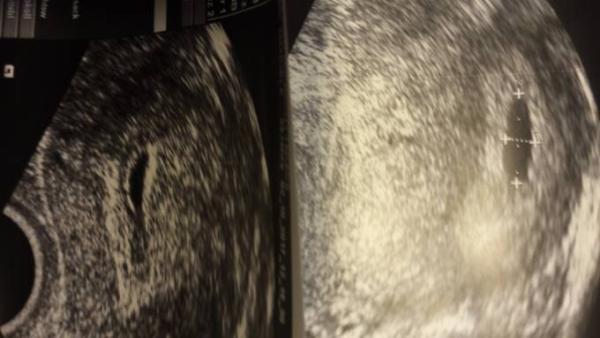

Schau dir mal die US Bilder an

das rechte ist von heute, das linke von letzter Woche

Ich kann auf dem linken Bild an der Seite Schatten erkennen. Was hat der Arzt den damals dazu gesagt? War da sicher was drin? Dottersack? Das Rechte Bild sieht leer aus, aber so sah Meine gestern im Schall auch erst aus und die Ärztin hat dann etwas suchen müssen. Dann konnte man aber alles gut sehen. Was hat dein Arzt denn gesagt beim letzten mal?

Eben gar nichts. Heute hat er gesagt dass man letzte Woche mehr sah als heute

Aber auf dem rechten Bild oben ist doch irgendwie ein Kreis zu erkennen oder nicht??

Ganz ehrlich.. ich seh da auch was oben im rechten Bild. Auf dem Laptop sieht man es eher als auf dem Handy.

Also ich meine jetzt in der Fruchthöhle. In der drin oben rechts

Ich könnte auch was erkennen ganz oben ist doch ein dottersack oder....

Wenn der Arzt aber bei dem Termin davor sicher einen Dottersack gesehen hat, dann ist es auch kein Windei. Die Fruchthülle war dann ja nicht leer von Anfang an.

Deshalb, wenn man jetzt nichts sieht, ist es entweder eine Fehlgeburt und es hat sich zurückentwickelt oder es ist ein Eckenhocker und man sah es einfach nur nicht.